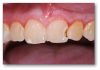

Example 1: Soft-Tissue Recontouring and Esthetics

The first example is of a mouth that needed soft-tissue recontouring with better esthetics (Figure 1). A diode laser is important for debridement, soft-tissue engineering, and better cleaning afterwards. The diode laser is popular in dentistry due to its small size and ease of use for minor soft-tissue surgery.1 It is a minimally invasive technology that offers advantages superior to those of the conventional scalpel, such as reduction of bleeding and inflammation and the lower probability of scars.2 Its effectiveness is comparable with that of other types of lasers, and it is an option of lower cost and greater ease of use.  Based on its photothermal effect, the diode laser is used for the removal of small lesions of the oral mucosa by excision or vaporization procedures.3

Fig 1. A patient was in need of soft-tissue recontouring and better esthetics.

Figure 1